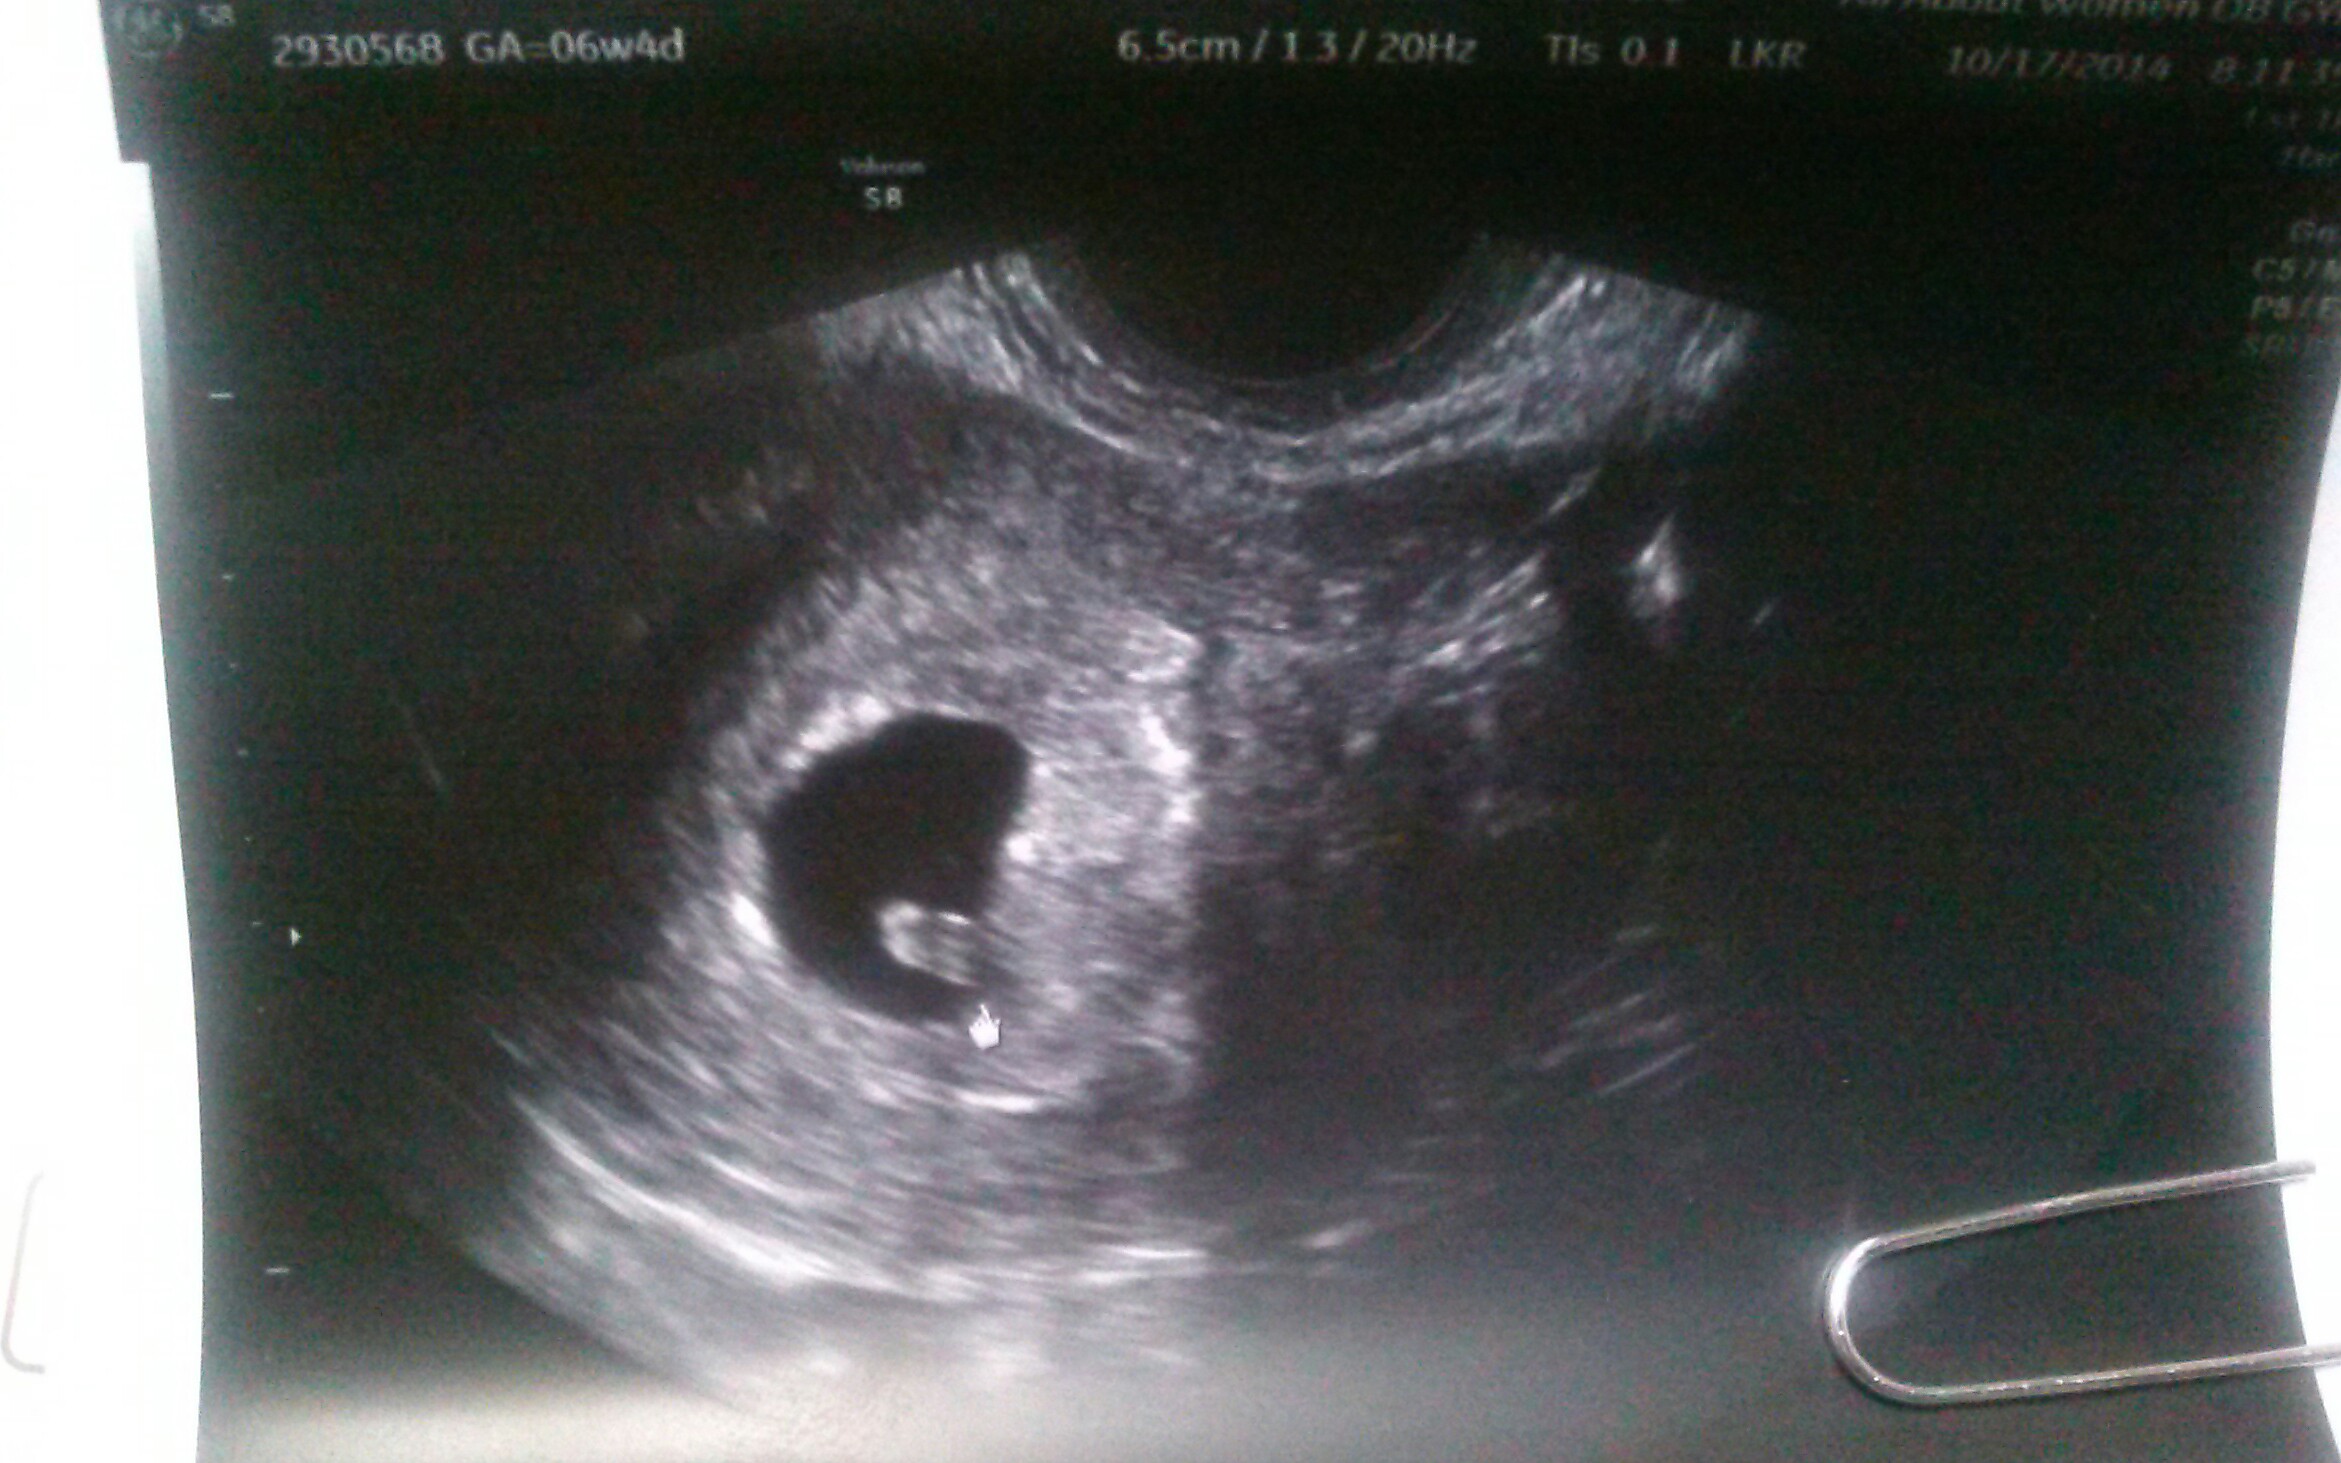

I had first US on 10-17. Sonographer said she was dating at 6 weeks exactly (I noticed on US pic it said 6w4d after I got home) I got to hear and see heartbeat. She said it was 110, but again pic said 115? She said everything was right on for being so early. I'm excited and I was still in shock and didn't hardly ask any questions. Next ultrasound is 11-13 at around 10 weeks. I'm still nervous!